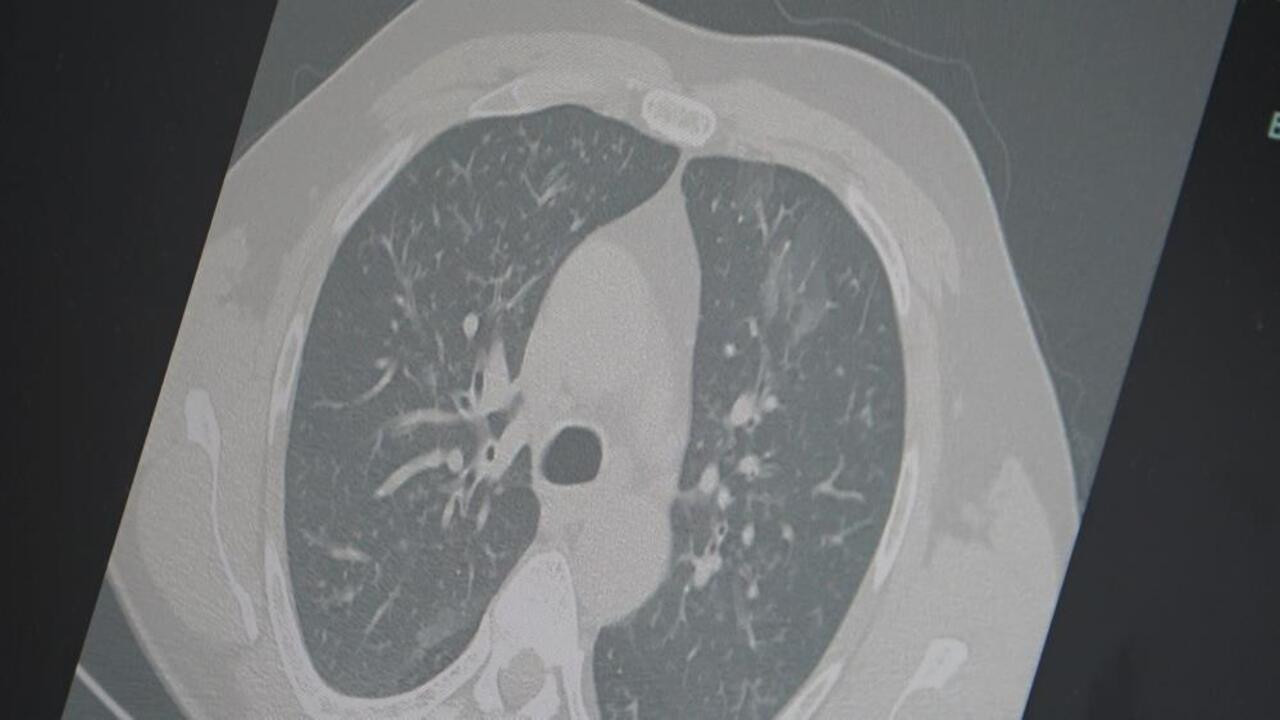

Dr. Özkaya, grip ve kovid 19'un zatürreye dönüşme riski taşıdığını önemle vurgulayarak, "Grip veya kovid sonrası birçok hastamızda hastalık akciğerlere iniyor ve zatürre olarak karşımıza çıkıyor. Hastaneye yatan hasta sayısında da artış gözlemliyoruz" şeklinde konuştu.

Salgının, sinsi bir şekilde yayıldığını ancak günlük hayatı tamamen durdurmadığını belirten Özkaya, şunları söyledi: "Grip ve kovid artık yatağa düşürecek kadar ağır seyretmese de günlük işlerimizi yapmayı zorlaştırıyor. Ne tam hasta ne de tam iyilik hali olmadan virüs toplumda dolaşmaya devam ediyor. Dinlenmeyen ve izolasyon uygulamayan vakalar bulaş zincirini sürdürüyor" ifadelerini kullandı. Prof. Dr. Özkaya, vatandaşlara yönelik olarak şu önerilerde bulundu: "En ufak grip benzeri şikayeti olan vatandaşlarımızın evlerinde dinlenmelerini öneriyoruz. Uzamış öksürük ve nefes darlığı yaşayanların ise mutlaka doktora başvurarak akciğer röntgeni çektirmeleri ve uygun tedaviyi almaları gerekiyor."